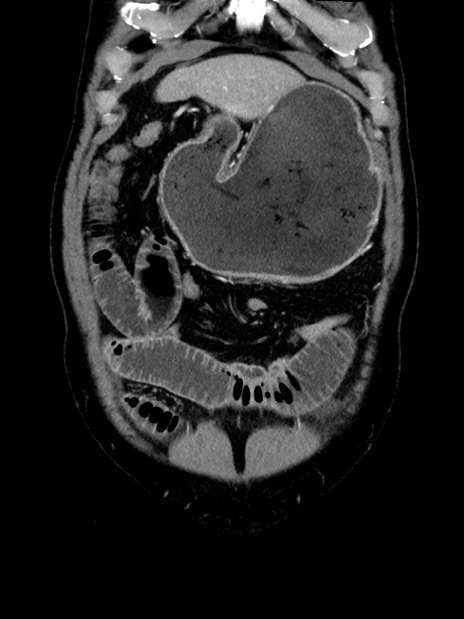

症例35(冠状断像)

【症例】70歳代 男性

【主訴】腹部膨満、嘔吐

【現病歴】昨日より腹部膨満感出現。本日増悪し、仙痛出現。嘔吐あり、受診。

【既往歴】糖尿病、胆摘後

【身体所見】BP 149/80mmHg、HR 74/min、BT 35.9℃、腹部:膨満、軟、圧痛なし。腸雑音減弱あり。上腹部正中切開瘢痕あり。

【データ】WBC 13500、CRP 1.72